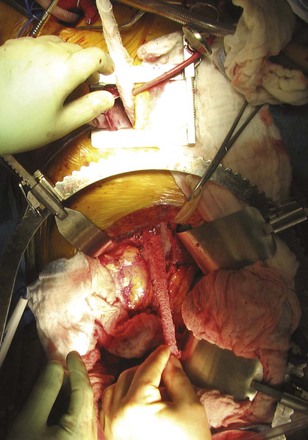

Figure 54–94 Exposure of large right upper pole tumor through a thoracoabdominal incision.

(Reproduced with permission from Novick AC, Streem SB, Pontes E, editors. Stewart’s operative urology. 2nd ed. Baltimore: Williams & Wilkins; 1989.)

For large renal tumors, especially those of the upper pole, the thoracoabdominal approach is preferable to an anterior approach (Fig. 54–92; see Fig. 54–93 on the Expert Consult website

). On the right side the liver is retracted cephalad. The hepatic flexure of the colon and the duodenum are reflected medially, exposing the IVC, the renal pedicle, and the anterior surface of the kidney (Figs. 54-94 to 54-96). The renal artery and vein are handled as described for the anterior approach. The ureter and right gonadal vein are ligated and divided. The kidney is mobilized outside the Gerota fascia down to the psoas fascia. The additional vascular attachments to the upper pole tumor and adrenal gland are exposed by medial retraction of the IVC along with caudal and lateral retraction of the kidney. They are ligated and divided. A curved-shaped clamp is passed along the superior portion of the adrenal gland to gain control of the phrenic vessels using a 0 silk suture ligature. The specimen is mobilized fully away from the liver and removed en bloc.